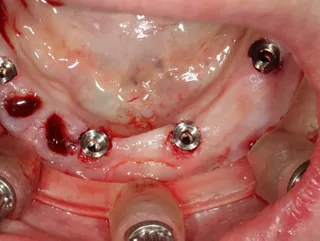

14. Positioning of the transfers in the lower jaw for impression.

15. The framework structure for the lower jaw ensures a precise fit on the 4 Axiom X3® TL implants.